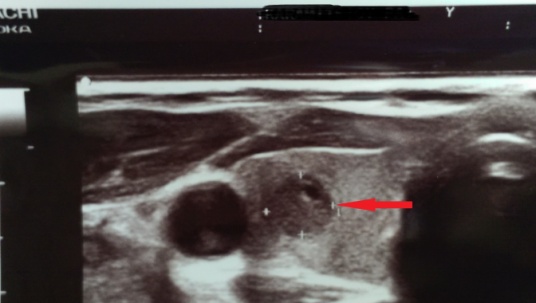

Neck ultrasound. Presence of a right inferior parathyroid adenoma (Courtesy Dr. V. Penopoulos)